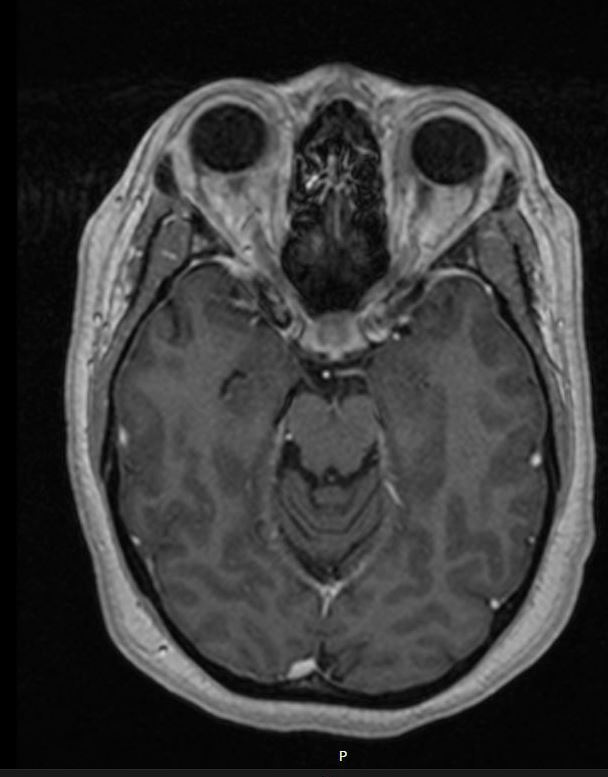

Case 5